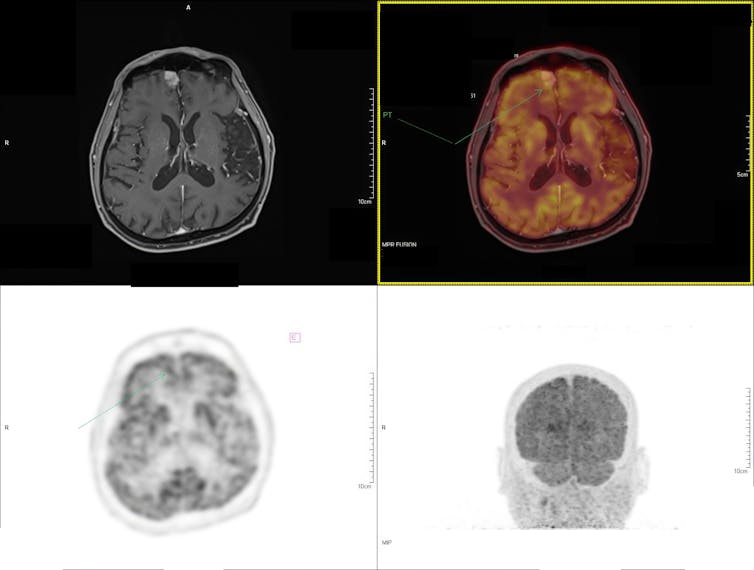

More than a century after de Hevesy’s experiments, many fields now routinely use radioactive tracers, from medicine to materials science and biology.

These tracers can monitor the progression of disease in medical procedures, the uptake of nutrients in plant biology, the age and flow of water in aquifers and the measurement of wear and corrosion of materials, among other applications. Radioisotopes allow researchers to follow the paths of nutrients and drugs in living systems without invasively cutting the tissue.